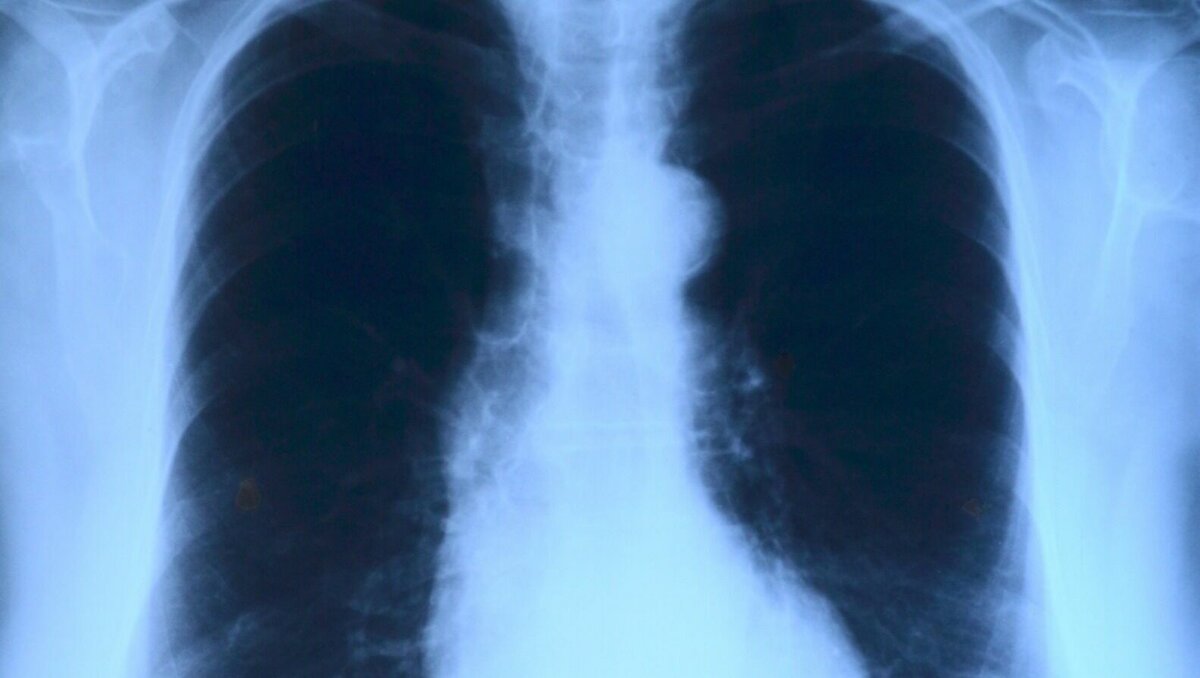

В Ростовской области за последние семь лет заболеваемость туберкулёзом снизилась вдвое, о профилактике и причинах болезни рассказали ростовские специалисты. Портал Rostov.Aif поговорил с донскими специалистами в преддверии Всемирного дня борьбы с туберкулезом и выяснил, настолько ли опасна болезнь в наши дни, и что следует знать о ней ростовчанам. Главный внештатный специалист по клинической фармакологии Минздрава Ростовской области Андрей Сафроненко рассказал, что в прошлом основной проблемой заболеваемости являлась резистентность[прим. редакции — невосприимчивость] микроорганизмов к противомикробным препаратам. Однако сейчас на рынке лекарств есть достаточно препаратов, способных вылечить туберкулёз. Врач-эпидемиолог ростовского Центра гигиены и эпидемиологии Диана Федорченко рассказала, что последние 15 лет в Ростове наблюдается снижение заболеваемости туберкулезом, а специалисты донского Минздрава и вовсе утверждают, что за последние семь лет количество случаев заражения сократилис

Врач-эпидемиолог ростовского Центра гигиены и эпидемиологии Диана Федорченко рассказала, что последние 15 лет в Ростове наблюдается снижение заболеваемости туберкулезом, а специалисты донского Минздрава и вовсе утверждают, что за последние семь лет количество случаев заражения сократились практически вдвое. Так, например, в 2022 году выявили около 1,2 тысячи заболевших туберкулёзом дончан — эти показатели на 10% ниже среднероссийских показателей того же года.

Врачи рекомендуют дончанам в качестве профилактики болезни проходить флюорографию не реже раза в два года, а также отслеживать свое состояние — в случае появления излишней утомляемости, потливости, потери веса и кашля с мокротой в течение более чем трех недель дончанам следует обратиться за медицинской помощью.